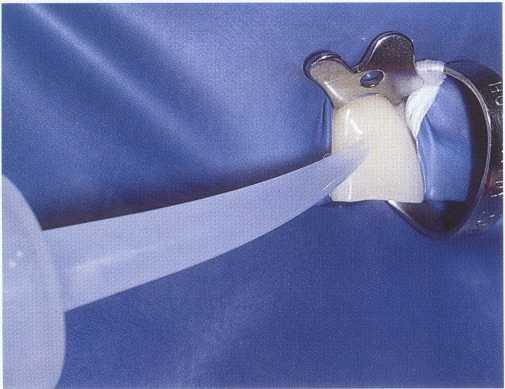

C02 snow is an excellent method of thermal testing because it provides a temperature of -50° C and transforms from a solid to a gaseous state, eliminating the potential for stimulation of adjacent teeth.

FIGURE 1-4 Dichlorodifluoromethane is also an effective method of cold testing. The material can be sprayed on a cotton pellet or cotton-tip applicator for use. As with C02 snow, it has no liquid state.